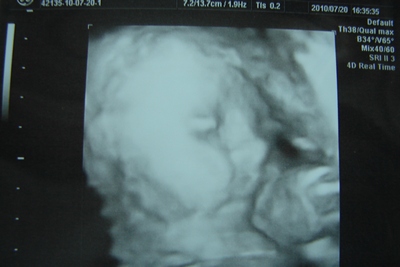

Várjuk a 4D-t, várjuk a 4D-t!!!

Jaj, de nem a Shrekket, azt már láttam és különben sem tudnál átverni vele, mert az csak 3D-s.

További szépséges és jó kismamiságot!